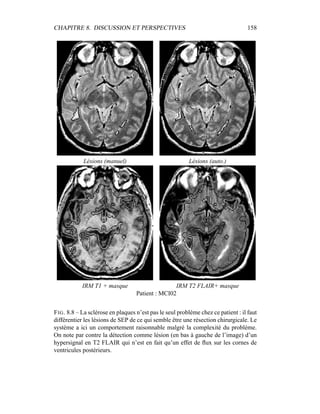

l’ellipse de Mahalanobis donné par 1

2

(X − µk)T

Σ−1

k (X − µk) = λ. Dans